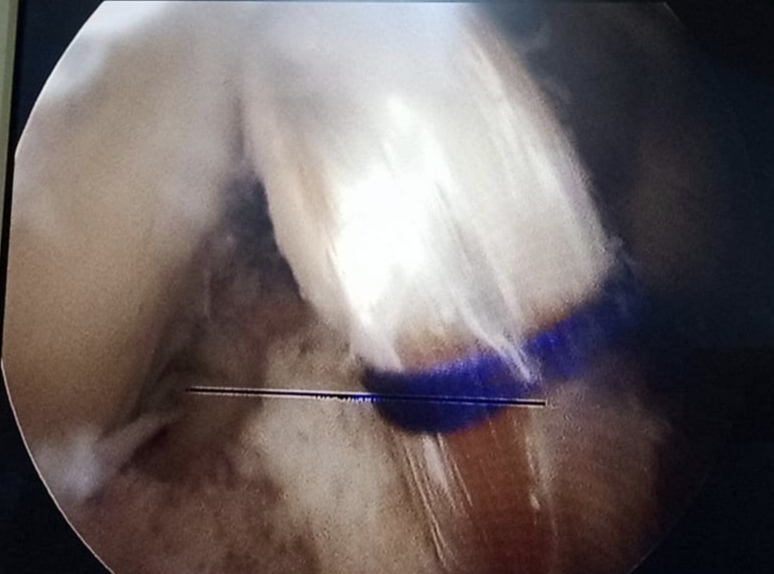

Warning: Graphic Content

The following section contains graphic images of surgical procedures. These images are intended for educational purposes and may be disturbing to some viewers. Viewer discretion is advised.

Surgeries